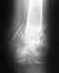

причём на весе, который не на одно повторение делал в зале.... Благо мышцы и связки все целые остались, поломал как раз в том месте где грудь крепится. Меня прооперировали вставили титановый штифт во внутрь кости, снизу и сверху закрепили болтами, врач сказал что можно штифт оставить. Вопрос: смогу ли я вообще выйти на те же веса в жиме и тяге, которые были до травмы и рости дальше в силовых? И третье стоит ли вообще снимать штифт, по крайней мере вытаскивать нижний болт, т.к. из-за него будет создаваться повышенная нагрузка на кость и не треснет ли она в том же месте? Правильно ли срастается кость? Ничего страшного что она сместилась немного и не приведёт ли это к перелому снова? снимок сделан спустя 3 недели после операции

Сделано все неплохо.